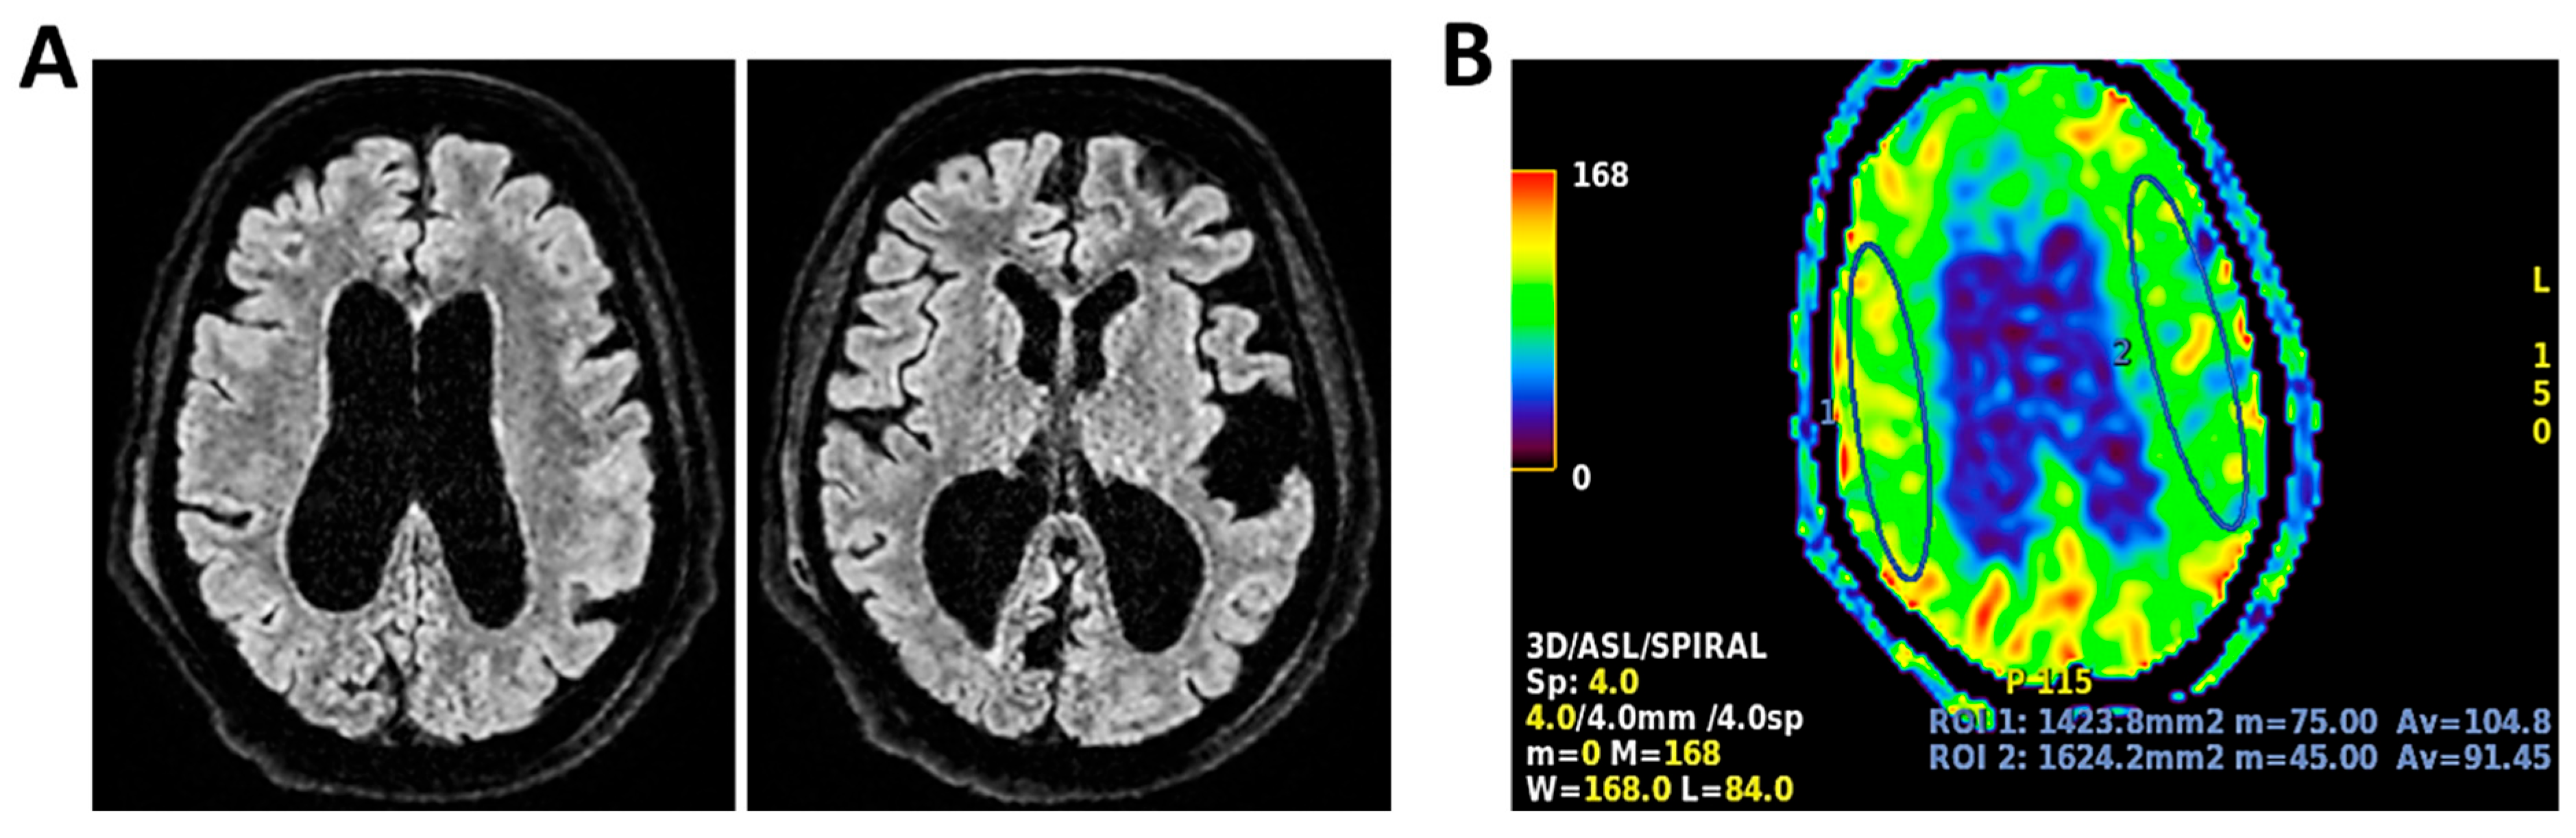

Figure 6.

MRI of patient 1 group 2. A 63-year-old man with a history of hypertension, dyslipidemia, and prior pulmonary lobectomy was admitted to the ER in a drowsy but verbally responsive state. His wife reported a recent episode of vomiting followed by loss of consciousness and tonic–clonic seizures. He was uncooperative and tremulous but afebrile, although a febrile episode had occurred in the preceding days. A lumbar puncture led to a diagnosis of Neisseria meningitidis type B meningitis. Ceftriaxone 2 g IV every 12 h was initiated. Brain CT, chest CT, and angio-CT of the epiaortic vessels showed no acute abnormalities. Due to clinical deterioration and a further seizure with hypotension, the patient was sedated, intubated, and experienced an episode of ventricular tachycardia during CT imaging, requiring IV Amiodarone. The patient was transferred to the ICU. On day 2, TCCD showed no significant flow abnormalities, with only mild asymmetry in PI (1.11 right, 1.4 left), without evidence of intracranial hypertension. (A) MRI exam with perfusion study reveal areas of altered signal intensity, hyperintense on 3D axial FLAIR sequence, (B) with diffusion restriction in axial DWI sequence, indicative of subacute inflammatory processes. These areas were scattered, the most significant is located along the subpial cortical surfaces of the left precentral and supramarginal gyri. Additionally, MRI exam demonstrates leveled material of likely inflammatory nature in both occipital horns of the lateral ventricles (A,B). (C) MRI perfusion with ASL sequence shows normal and symmetrical CBF values. Blue circles indicate the region of interest (ROI) used for quantitative CBF analysis.

Figure 7.

MRI of patient 2 group 2. A 45-year-old male without prior clinical conditions experienced chills and general discomfort and dizziness. He arrived at the ER unresponsive with a GCS score of 10. A brain CT scan showed no signs of hemorrhage or thrombosis, and a lumbar puncture was carried out for microbiological and biochemical analysis. Empirical therapy with Rocephin, Zovirax, and Ampicillin was initiated, and both neurology and intensive care consultations were obtained. Given the likely progressive clinical condition, the patient was sedated, intubated, and transferred to the ICU for further treatment. On the second day, the patient underwent a TCCD, which documented a PI of 1.32 on the right and 1.28 on the left (A) 3D axial FLAIR, (B) axial DWI and (C) 3D axial T1 FSPGR after administration of contrast medium demonstrate normal morphology and signal intensity of brain tissue. No evidence of acute or chronic infarction, demyelination or mass lesion. Supratentorial and infratentorial ventricular system is normal in size and configuration, with no midline shift or hydrocephalus. No signs of intracranial hypertension. Sulci and subarachnoid spaces are within normal limits for age. (D) MRI perfusion with ASL sequence shows normal and symmetrical CBF values. Blue circles indicate the ROI used for quantitative CBF analysis.

Etiological diagnoses were heterogeneous: meningococcal meningitis (n = 1, 20%) (case 1), PML (n = 1, 20%) (case 2), Listeria monocytogenes meningoencephalitis (n = 1, 20%) (case 3), meningoencephalitis of undetermined origin (n = 1, 20%) (case 4), and pneumococcal meningitis (n = 1, 20%) (case 5). Patients underwent MRI with ASL to assess cerebral perfusion. Three patients had normal TCCD findings (PI ≤ 1.4) and symmetrical CBF (differences <15% between hemispheres). ASL imaging confirmed the absence of perfusion deficits, even in cases where FLAIR imaging revealed mild inflammatory changes. All three patients recovered their baseline neurological function at 28 days (Table 3 and Figure 6, Figure 7 and Figure 8).